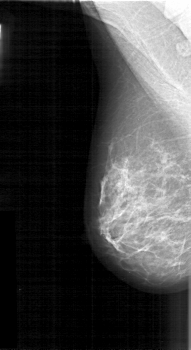

D_4119_1.RIGHT_CC

RIGHT_CC LINES 5221 PIXELS_PER_LINE 2566 BITS_PER_PIXEL 12 RESOLUTION 43.5 NON_OVERLAY